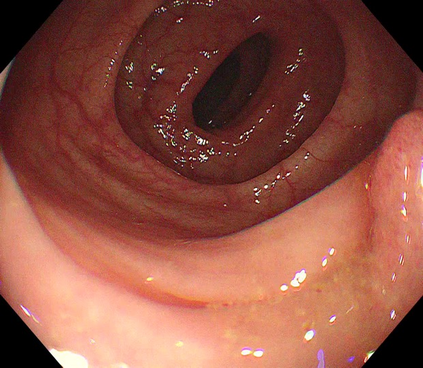

Polyps are early cancer indicators, so assessing occurrences of polyps and their removal is critical. They are observed through a colonoscopy screening procedure that generates a stream of video frames. Segmenting polyps in their natural video screening procedure has several challenges, such as the co-existence of imaging artefacts, motion blur, and floating debris. Most existing polyp segmentation algorithms are developed on curated still image datasets that do not represent real-world colonoscopy. Their performance often degrades on video data. We propose a video polyp segmentation method that performs self-supervised learning as an auxiliary task and a spatial-temporal self-attention mechanism for improved representation learning. Our end-to-end configuration and joint optimisation of losses enable the network to learn more discriminative contextual features in videos. Our experimental results demonstrate an improvement with respect to several state-of-the-art (SOTA) methods. Our ablation study also confirms that the choice of the proposed joint end-to-end training improves network accuracy by over 3% and nearly 10% on both the Dice similarity coefficient and intersection-over-union compared to the recently proposed method PNS+ and Polyp-PVT, respectively. Results on previously unseen video data indicate that the proposed method generalises.